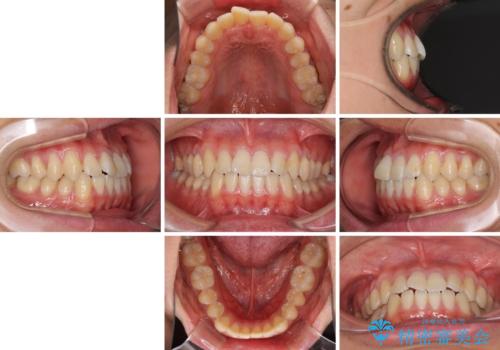

- 上下前歯のデコボコを気にして来院された患者様です。

叢生は軽微であり、費用を抑えて期間もあまりかけずに治療をしたいとのことで、インビザライン・ライトを用いて矯正治療を行うこととしました。

途中通院できなくなり、マウスピースの装着もしっかりとできなかったため、治療期間が長くかかってしまいました。